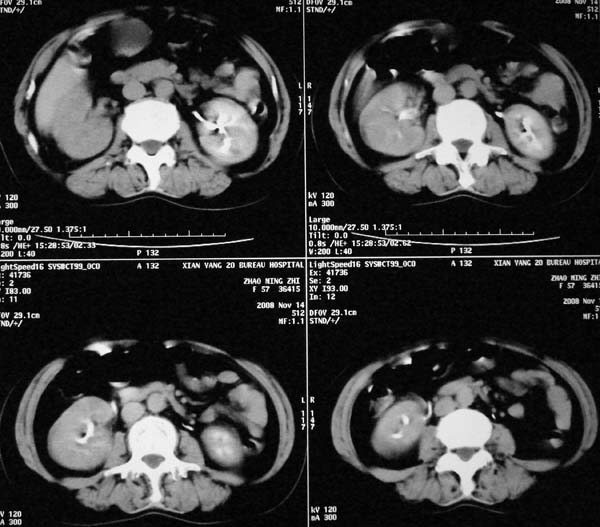

以下是引用dr.yang在2008-11-9 21:56:00的发言:[br]右肾上极占位?建议增强

以下是引用x-man在2008-11-9 22:30:00的发言:[br]建议先增强,右肾影明显增大,上极见边不清低密度肿块影,肿瘤待定.

以下是引用卜一在2008-11-10 8:09:00的发言:[br]建议先增强,右肾影明显增大,上极见边不清低密度肿块影,肿瘤待定.支持!另:第一次碎石是否肾受到损伤?合并感染?不知第一次碎石前是否做过彩超?

以下是引用dsl555在2008-11-9 23:57:00的发言:[br]建议先增强,右肾影明显增大,上极见边不清低密度肿块影,肿瘤待定. [br] [br]